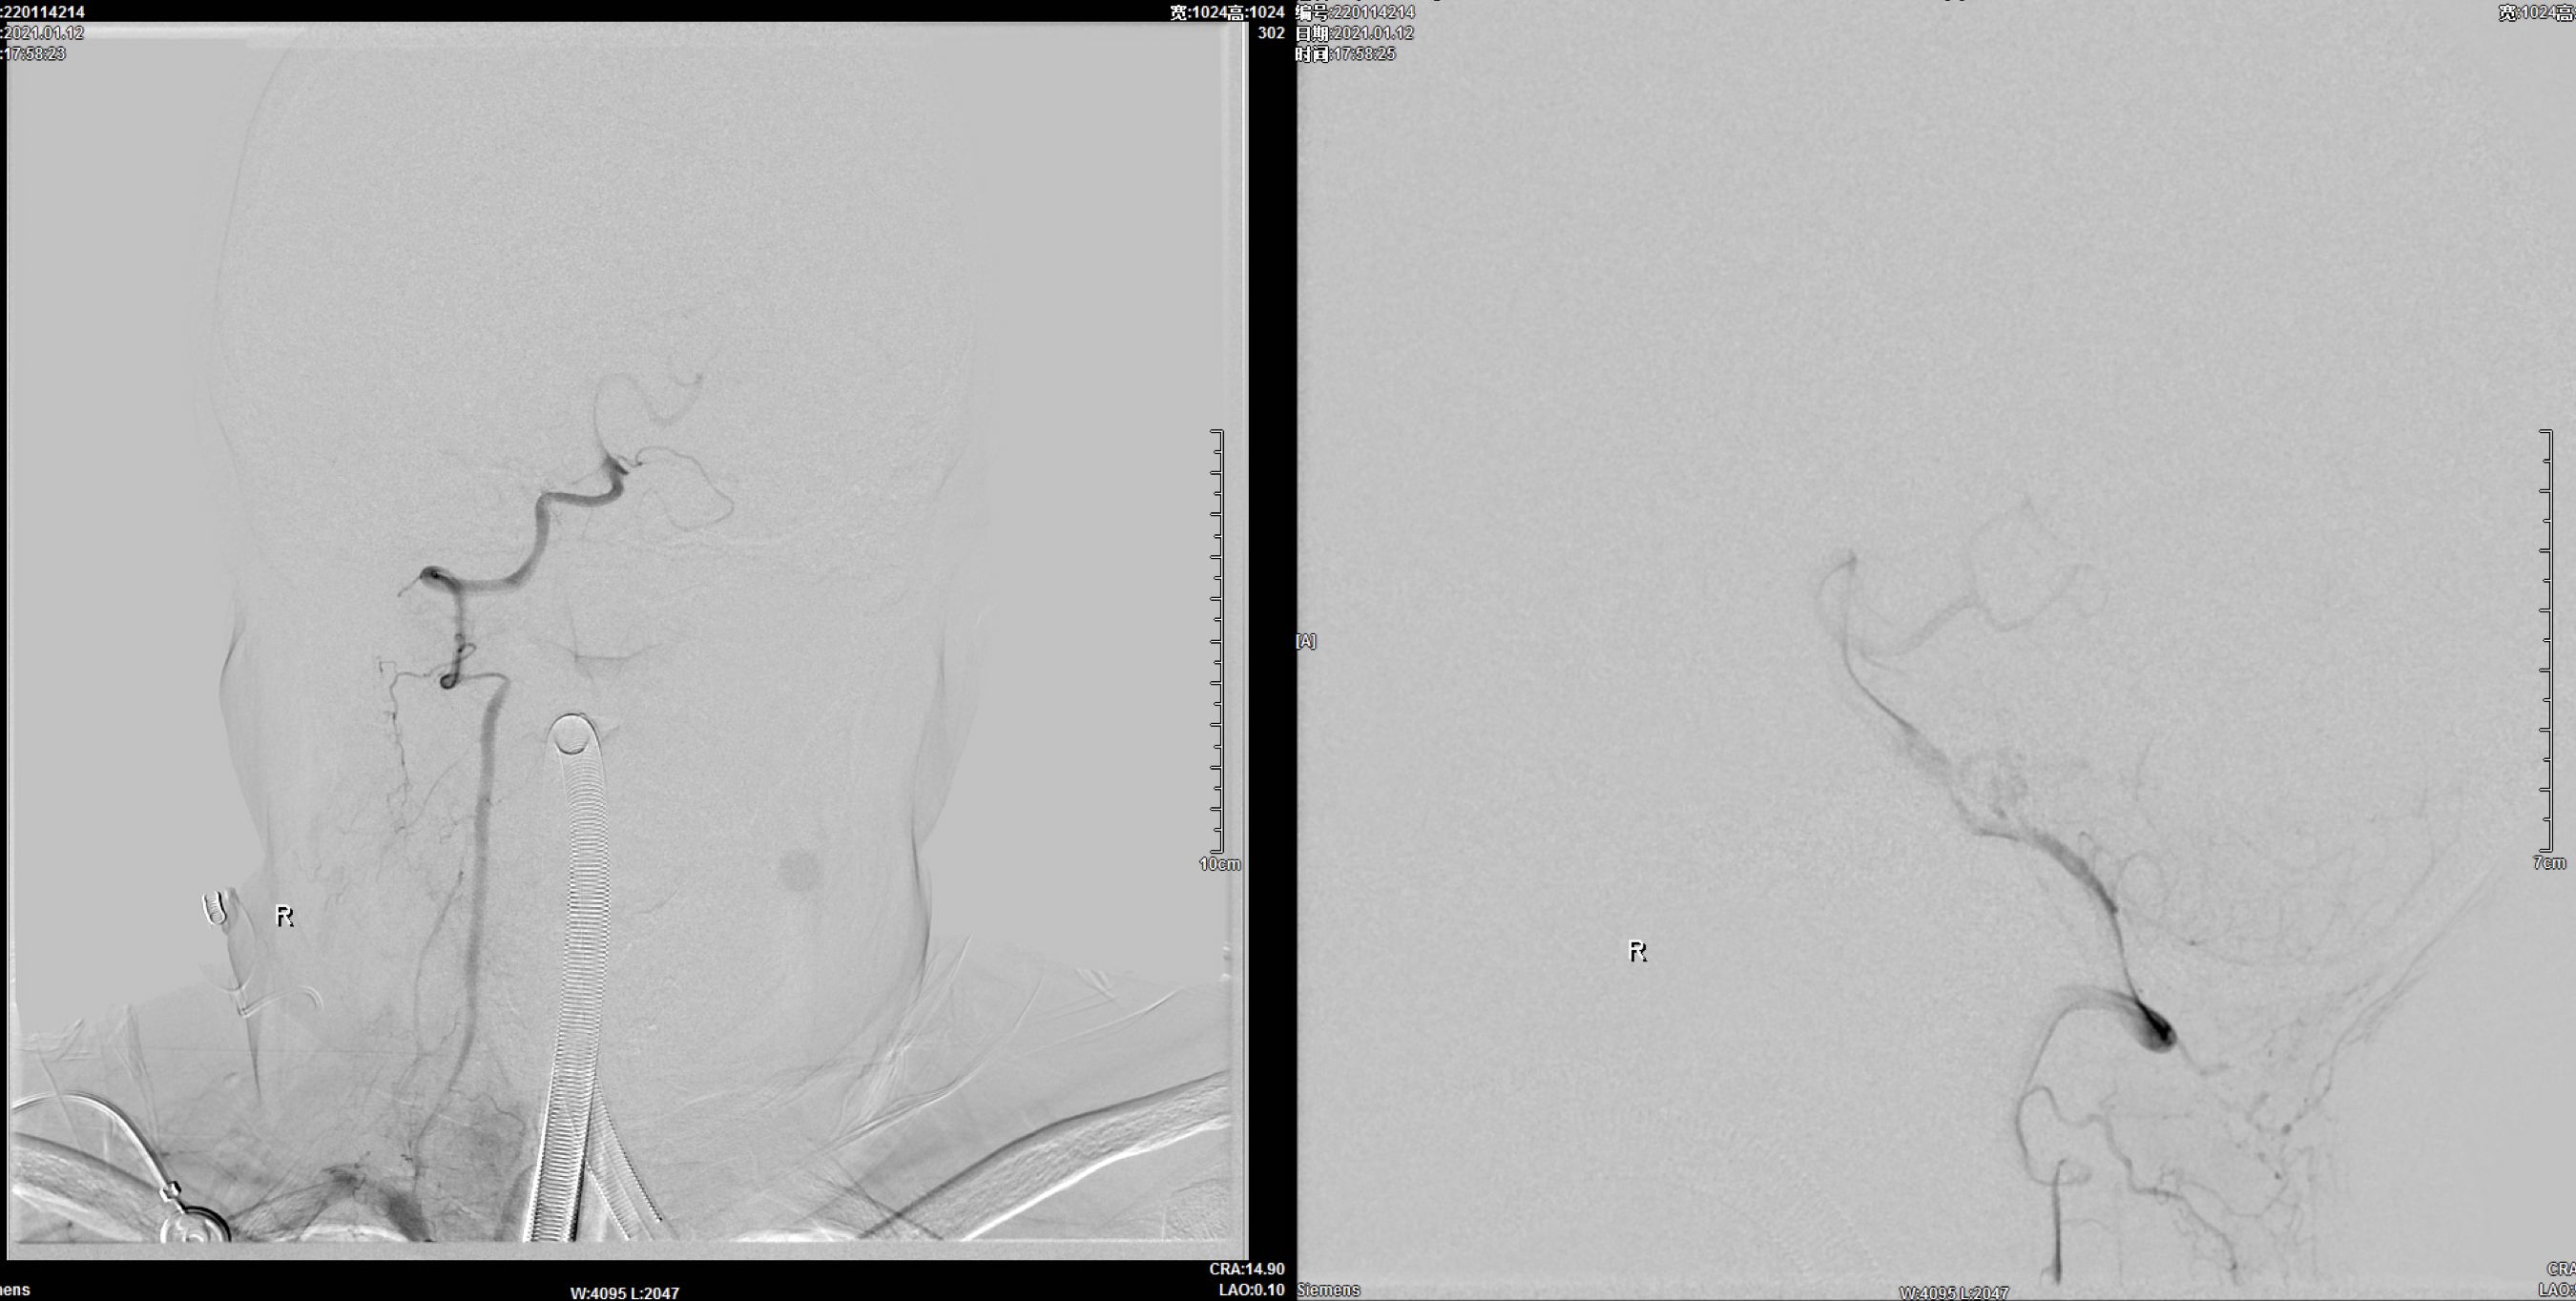

术后即刻正位造影:动脉瘤栓塞满意!

术后即刻侧位造影:动脉瘤栓塞满意!

术后三维重建:动脉瘤栓塞满意,后交通动脉保留!

朮后第二天复查头颅CT:颅内未见明显异常!